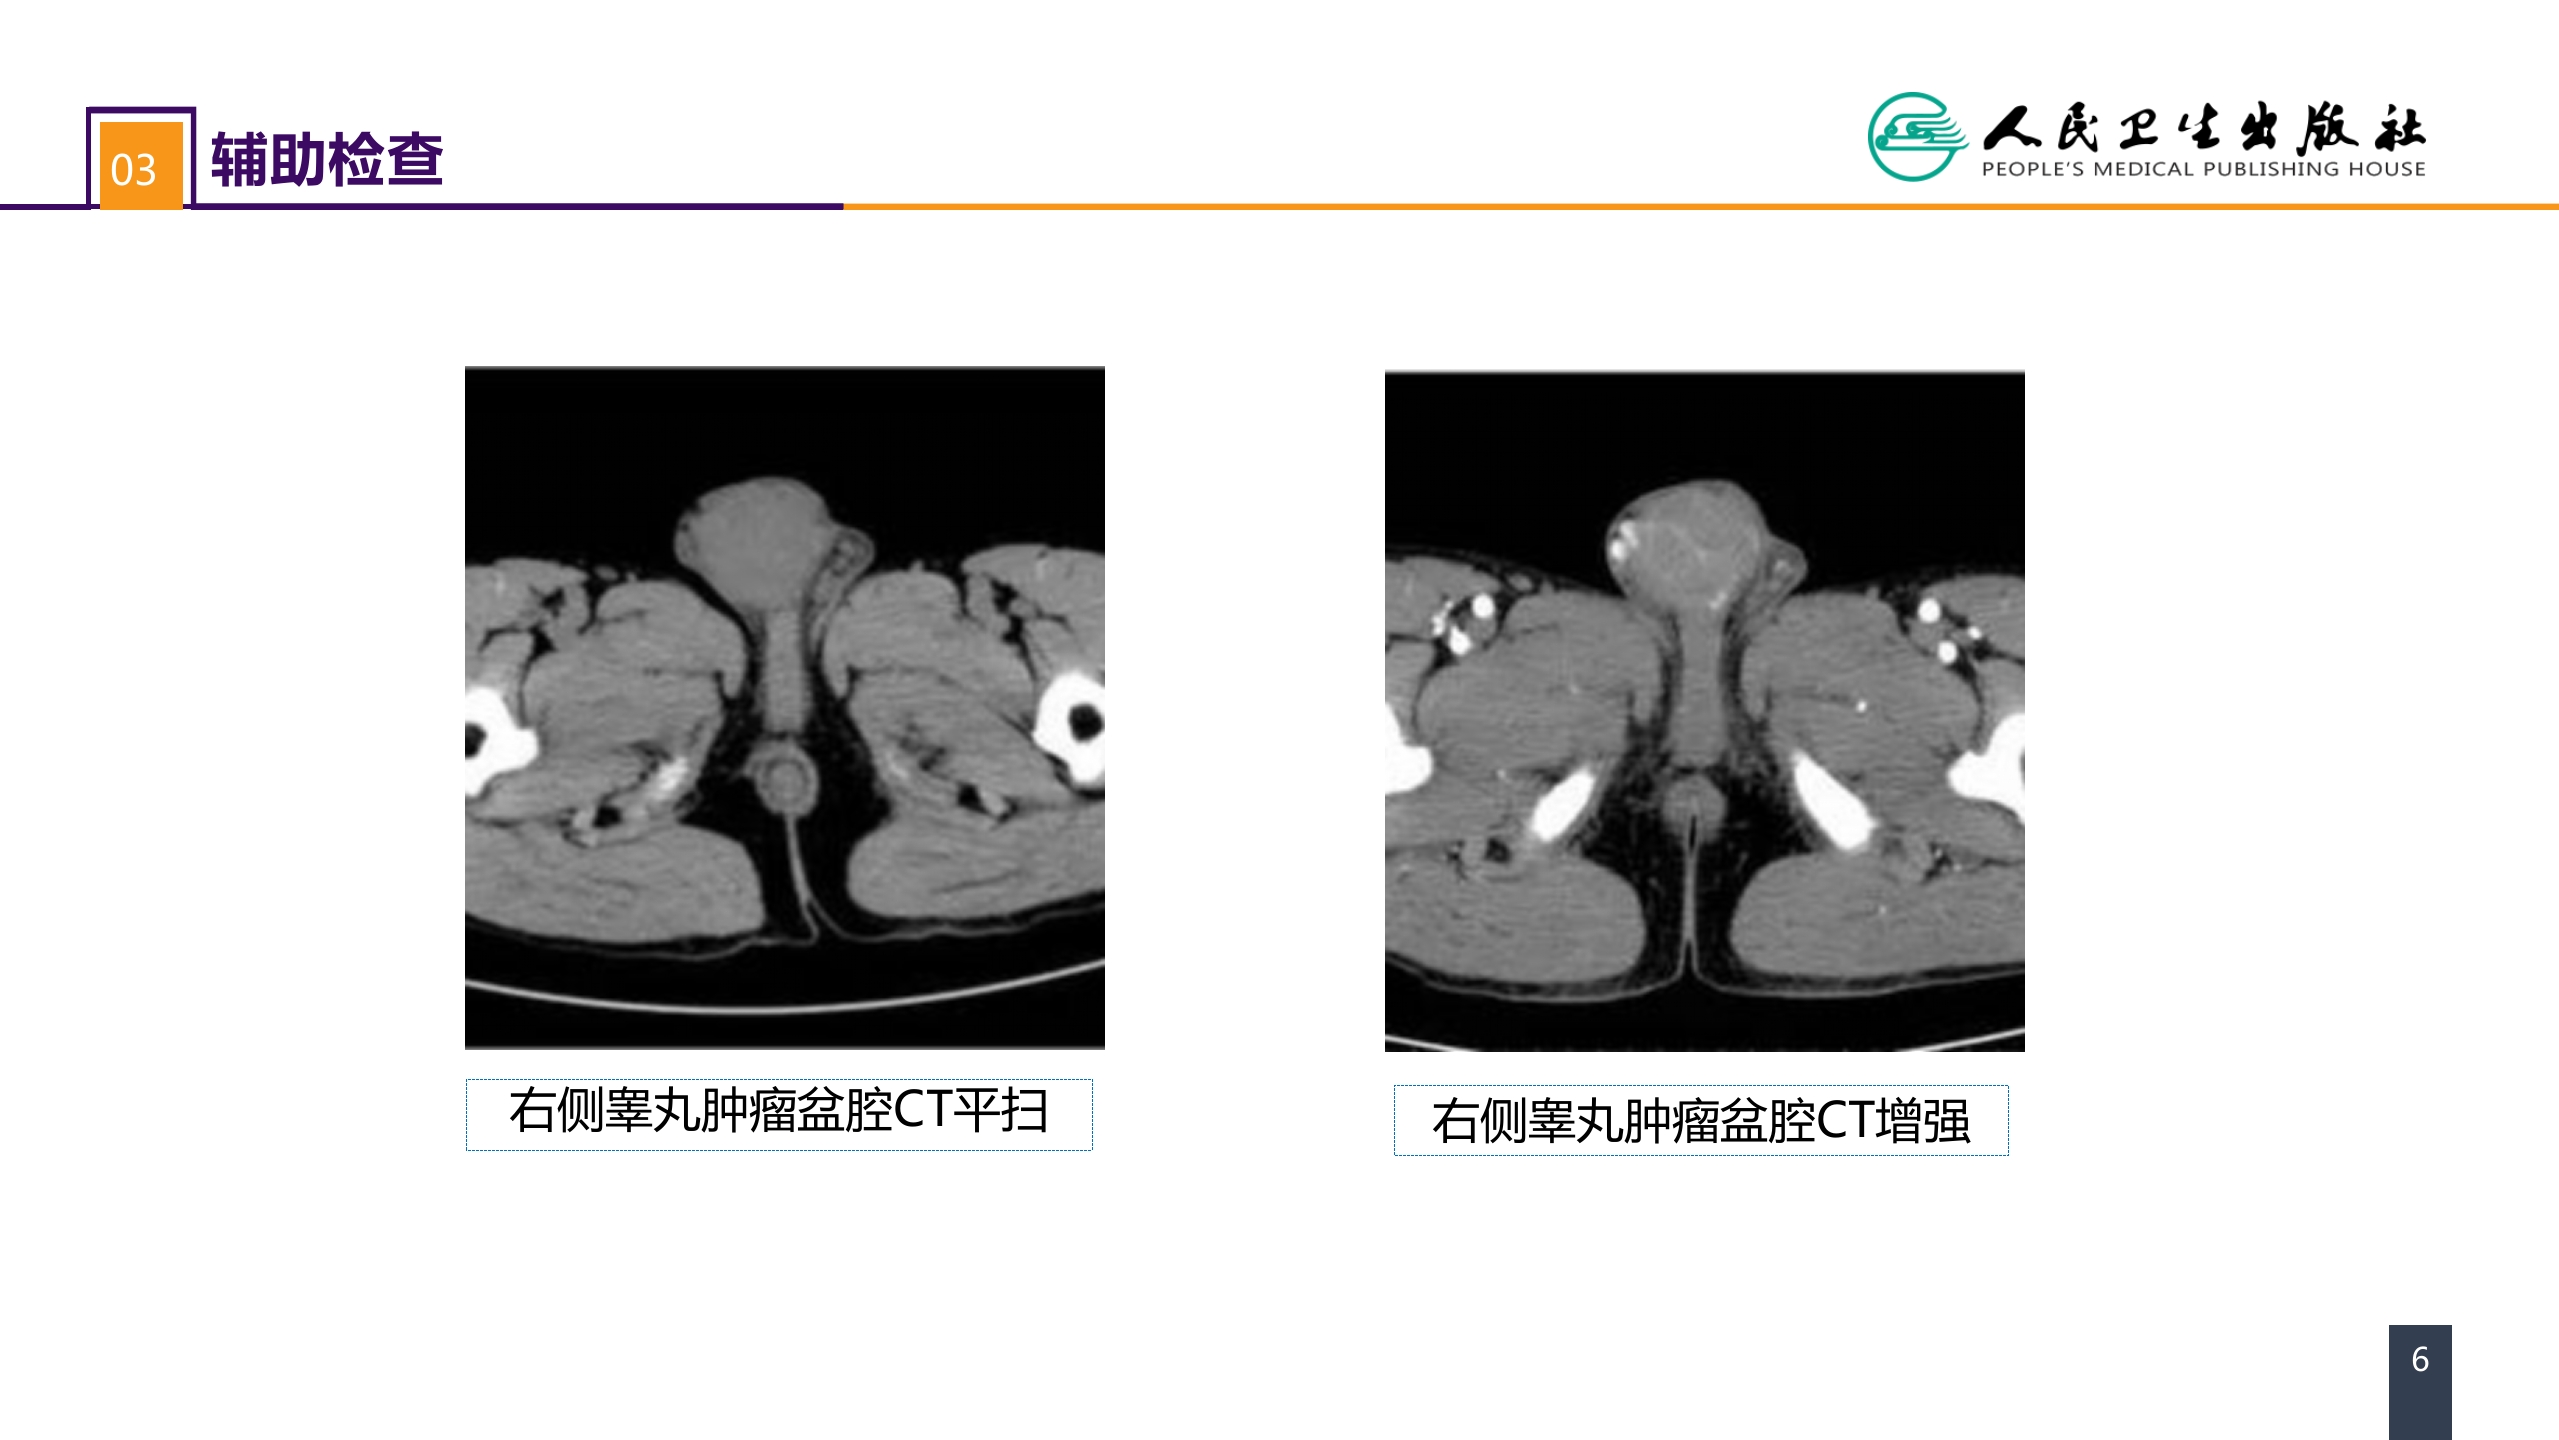

第五十三章 泌尿、男生殖系统肿瘤 案例分析-睾丸肿瘤